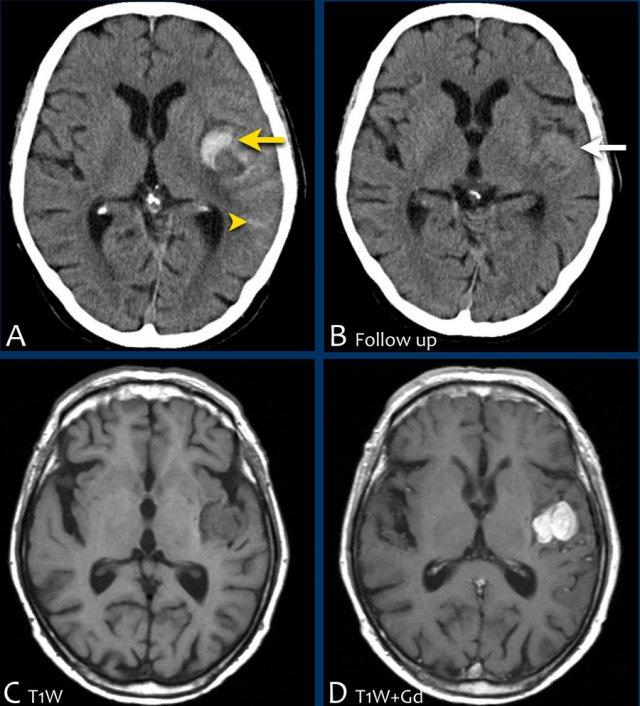

Các hình ảnh cho thấy xuất huyết do tăng huyết áp điển hình tại nhân bèo (putamen), là phần lớn nhất và nằm ngoài cùng của hạch nền.

Tiếp tục xem các hình ảnh theo dõi…

Trên phim chụp theo dõi, chỉ thấy mất nhu mô tại nhân bèo – nơi xuất huyết đã xảy ra (mũi tên).

Ba hình ảnh đầu tiên cho thấy khối tụ máu lớn tại hạch nền bên phải kèm phù não lan rộng.

Hình ảnh theo dõi một năm sau cho thấy hình ảnh hang hóa dạng tuyến tính do mất mô (mũi tên) và giảm tỷ trọng hạch nền là hậu quả của xơ hóa thần kinh đệm (gliosis).